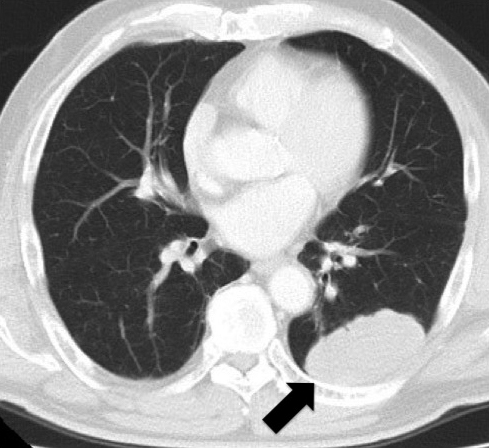

胸腹部CT所見:左下葉に57×34 mmの腫瘤性病変を認めた(Fig. 1).有意な縦隔リンパ節腫大なし.腹腔内には再発所見を認めず,癒着性イレウスと診断した.

Chest CT scan showed a tumor 5.7×3.4 cm in size in the lower lobe of the left lung (arrow) 17 years after the first operation.